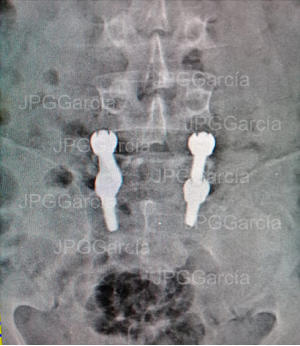

Instrumentación Lumbar Posterior por Espondilolistesis

Degenerativa (vistas lateral y anteroposterior)

Instrumentación Lumbar

Posterior por Espondilolistesis

Degenerativa (vistas lateral y

anteroposterior)